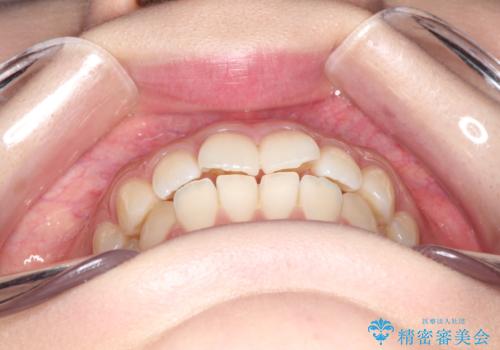

前歯のがたつきをインビザラインで目立たない矯正

- 上下の前歯のがたつきを主訴に来院されました。

マウスピースでの矯正を希望されたので、インビザラインで矯正治療を行うこととしました。

インビザラインではシュミレーションによりどのように歯が動くかを確認して矯正することができるので、患者様も安心して矯正をすることができました。